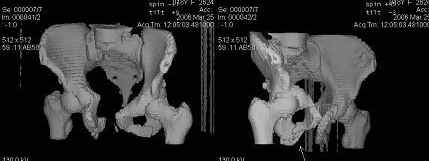

Re: Неправильно сросшийся перелом костей таза

Предоставляю срезы. Если пациентку функционально ничего не беспокоит, стоит ли навязывать ей лечение.